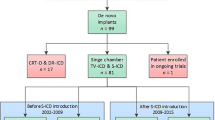

This study enrolled patients who met the aforementioned inclusion criteria in Zhongshan Hospital, Fudan University from August 21, 2018 to January 28, 2022. A total of 47 patients were enrolled consecutively, with a median follow-up duration of 554 days. The clinical characteristics of all patients are summarized in Table 1. Briefly, the majority of the patients were male (78.7%) with the median age of 39 years (IQR: 28, 61). The S‑ICDs were implanted in patients eligible for ICD implantation but without predictable pacing requirements [12] and for various etiologies (e.g., ischemic cardiomyopathy, dilated cardiomyopathy, hypertrophic cardiomyopathy, etc.). Overall, 70.2% of the patients underwent implantation for secondary prevention, with a median left ventricular ejection fraction (LVEF) of 48% (IQR: 35%, 65%). Four of the 47 patients were highly advised to receive S‑ICD implantation because of the high risk of infection associated with TV-ICD (one patient with previous TV-ICD-related infection and three with end-stage renal disease). Among the 47 patients considered suitable for S‑ICD implantation, 46 patients had > 1 appropriate vector in both postures (three appropriate vectors in 57.4% of the patients).

The leads were positioned to the right sternal border in half of the patients, which were determined by both preoperative fluoroscopy and sensing vector tests. Additionally, the increased number of implantations was accompanied by decreased procedure time (Fig. 1).